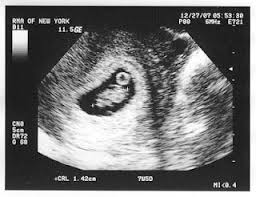

Tanda Tanda Awal Kehamilan

Tanda tanda awal kehamilan. Berikut adalah 10 tanda awal kehamilan yang boleh diperhatikan sebelum menjelang tarikh jangkaan haid anda. Ketahui lebih dini dan lekas beri perhatian ekstra. Pada tahap awal biasanya payudara mulai berubah karena bersiap untuk menghasilkan asi.

Ternyata ada juga beberapa gejala atau tanda tanda kehamilan lainnya yang muncul sebelum kamu telat haid. Cara akurat mendeteksi tanda awal kehamilan adalah dengan menggunakan alat tes kehamilan. Konstipasi susah buang air bisa menjadi tanda tanda awal kehamilan.